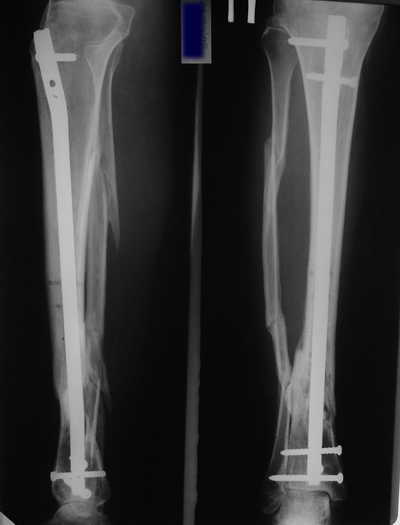

остеотомия м\б кости, аппарат Илизарова. По рентгенограммам в двух проекциях

произведено планирование устранения смещений (рис 2 и 3), между вторым и

третьим кольцом установлены 6 телескопических дистракторов Гесапода, данные

введены в программу, и далее втечение 10 дней больная подкручивала телескопы

согласно выданной компьютером инструкции. По завершению репозиции